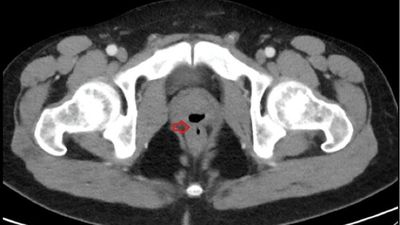

Mjekët zbuluan se ai kishte një lidhje jonormale midis prostatës dhe rektumit të tij që po bënte që sperma e tij të dilte nga një “grykë e papritur”.

Mjekët thanë se gjendja e burrit - një fistulë rektale-prostate - është shkaktuar në përgjithësi nga operacioni ose kushtet inflamatore si ajo e Crohn.